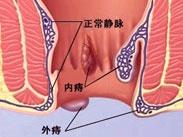

- 就诊科室:普通外科

- 传染性:无